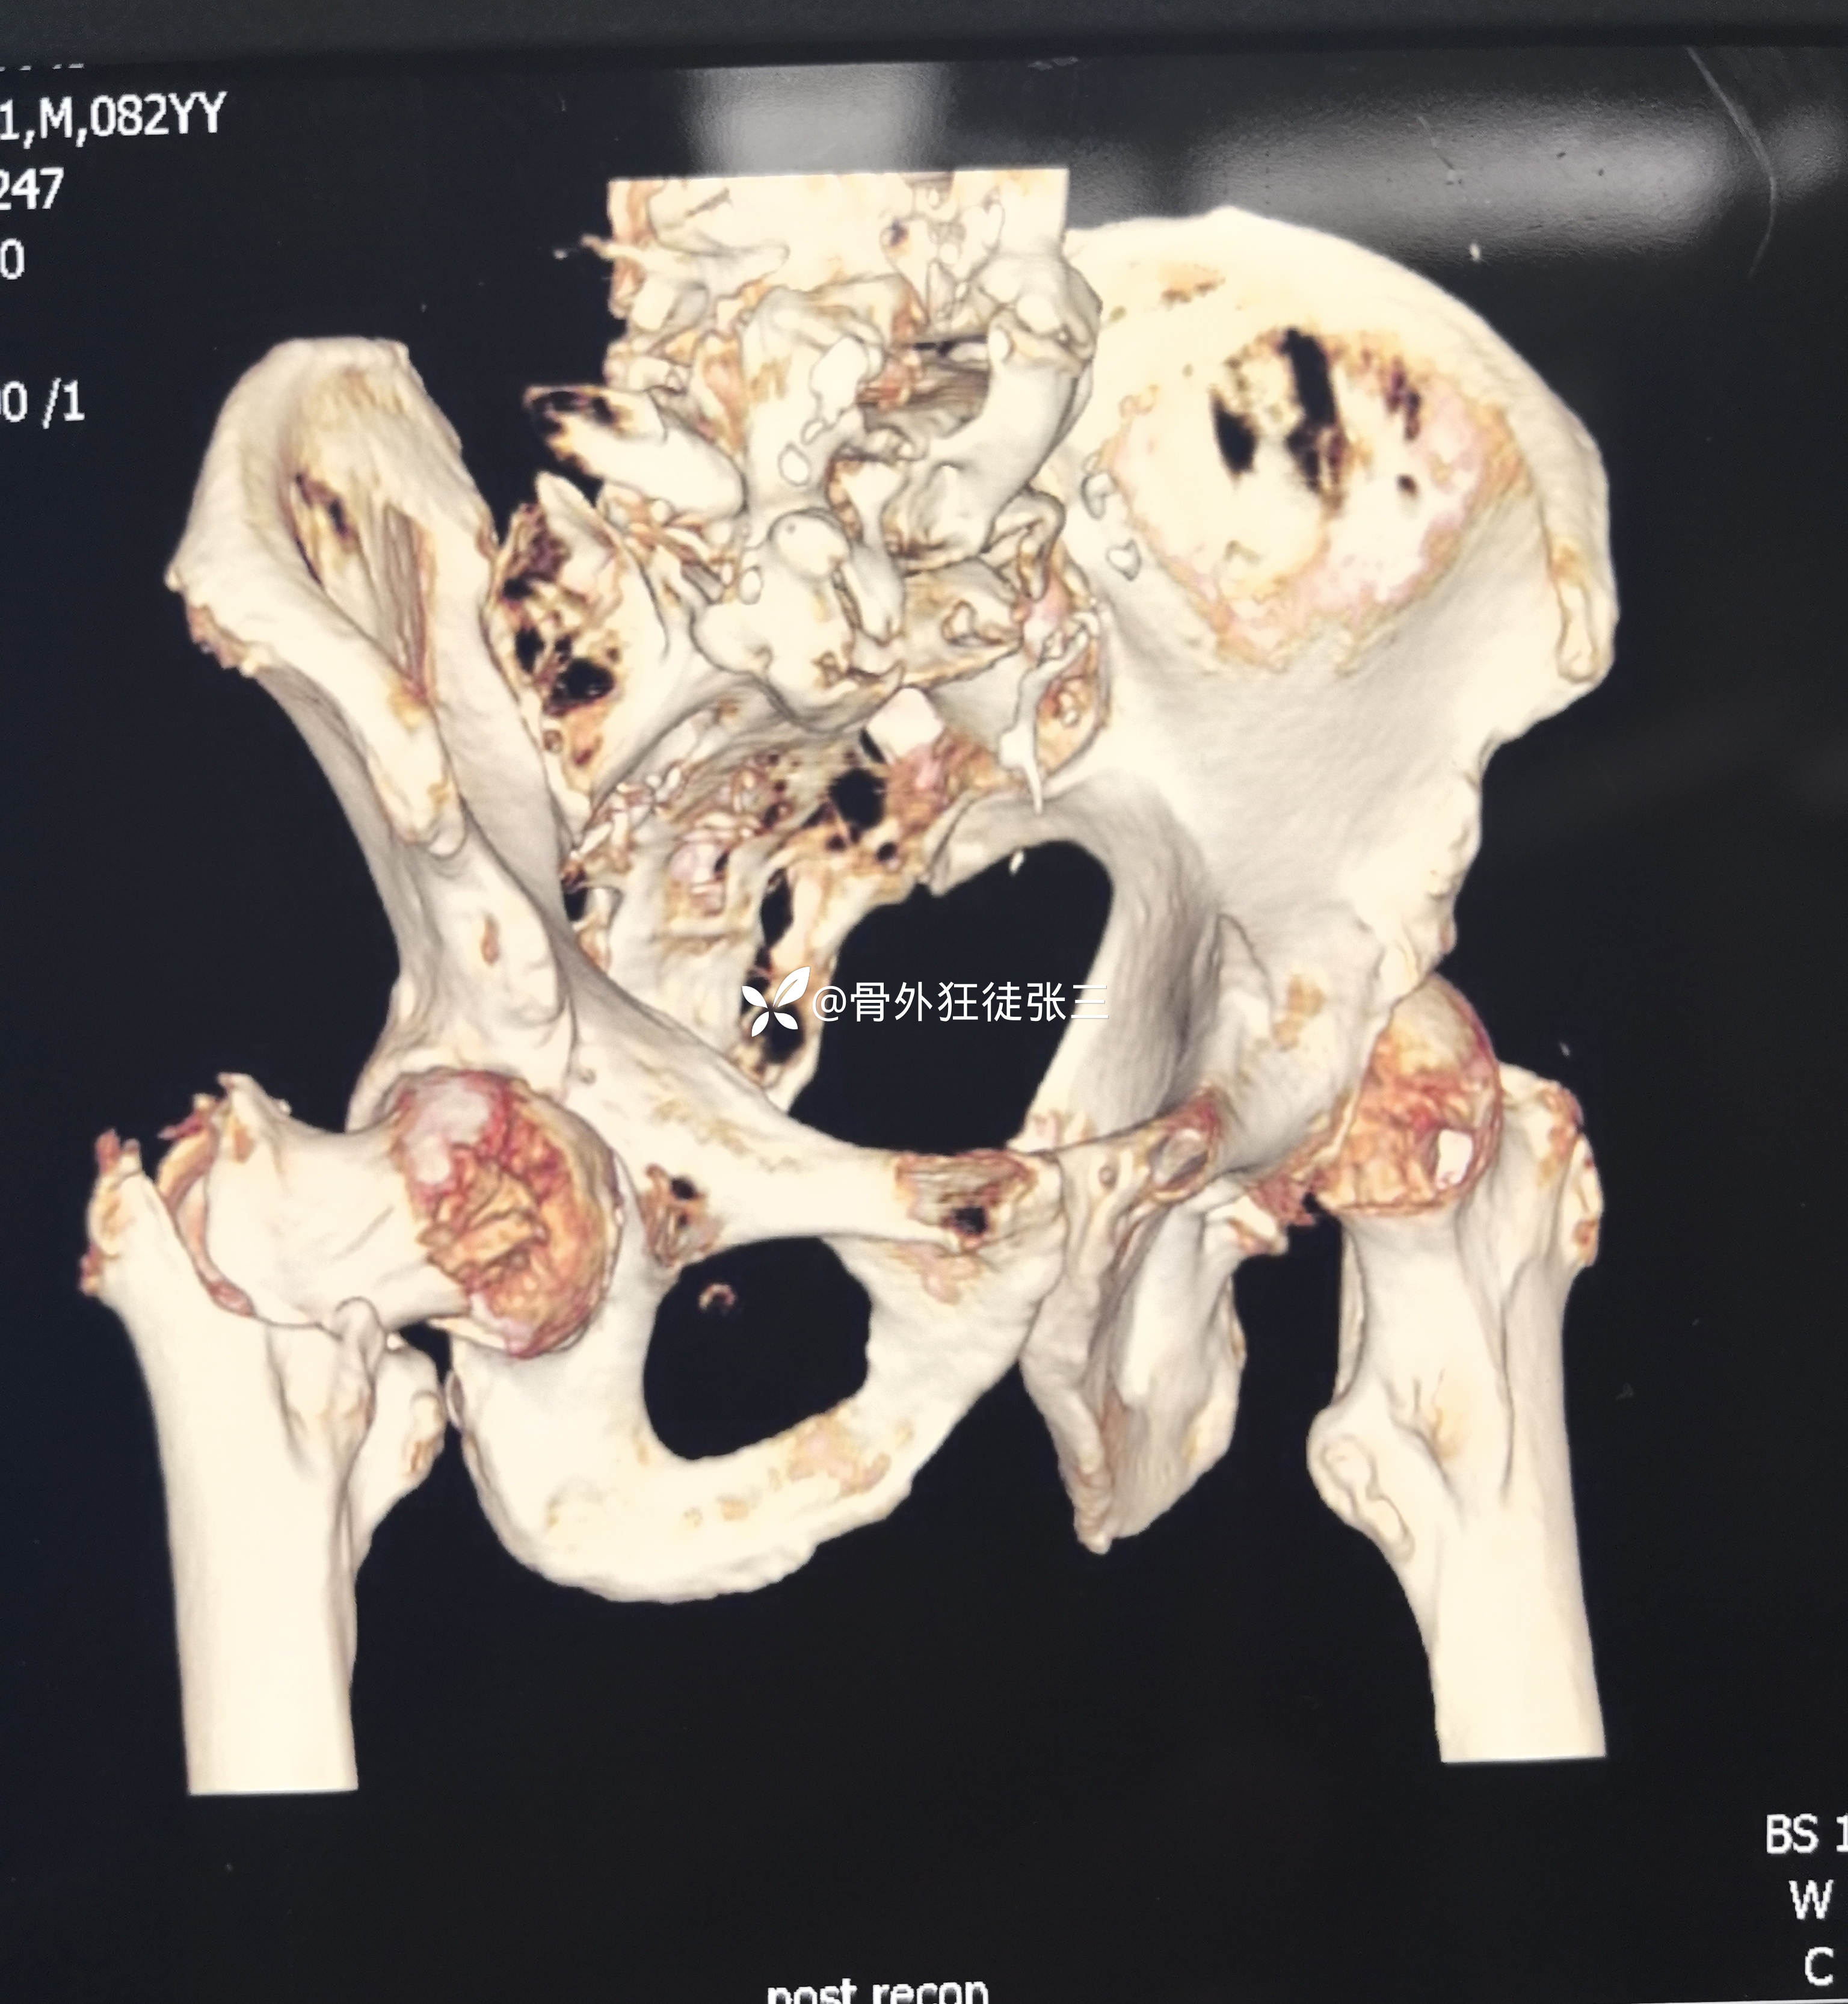

辅助检查:

右股骨转子间骨折